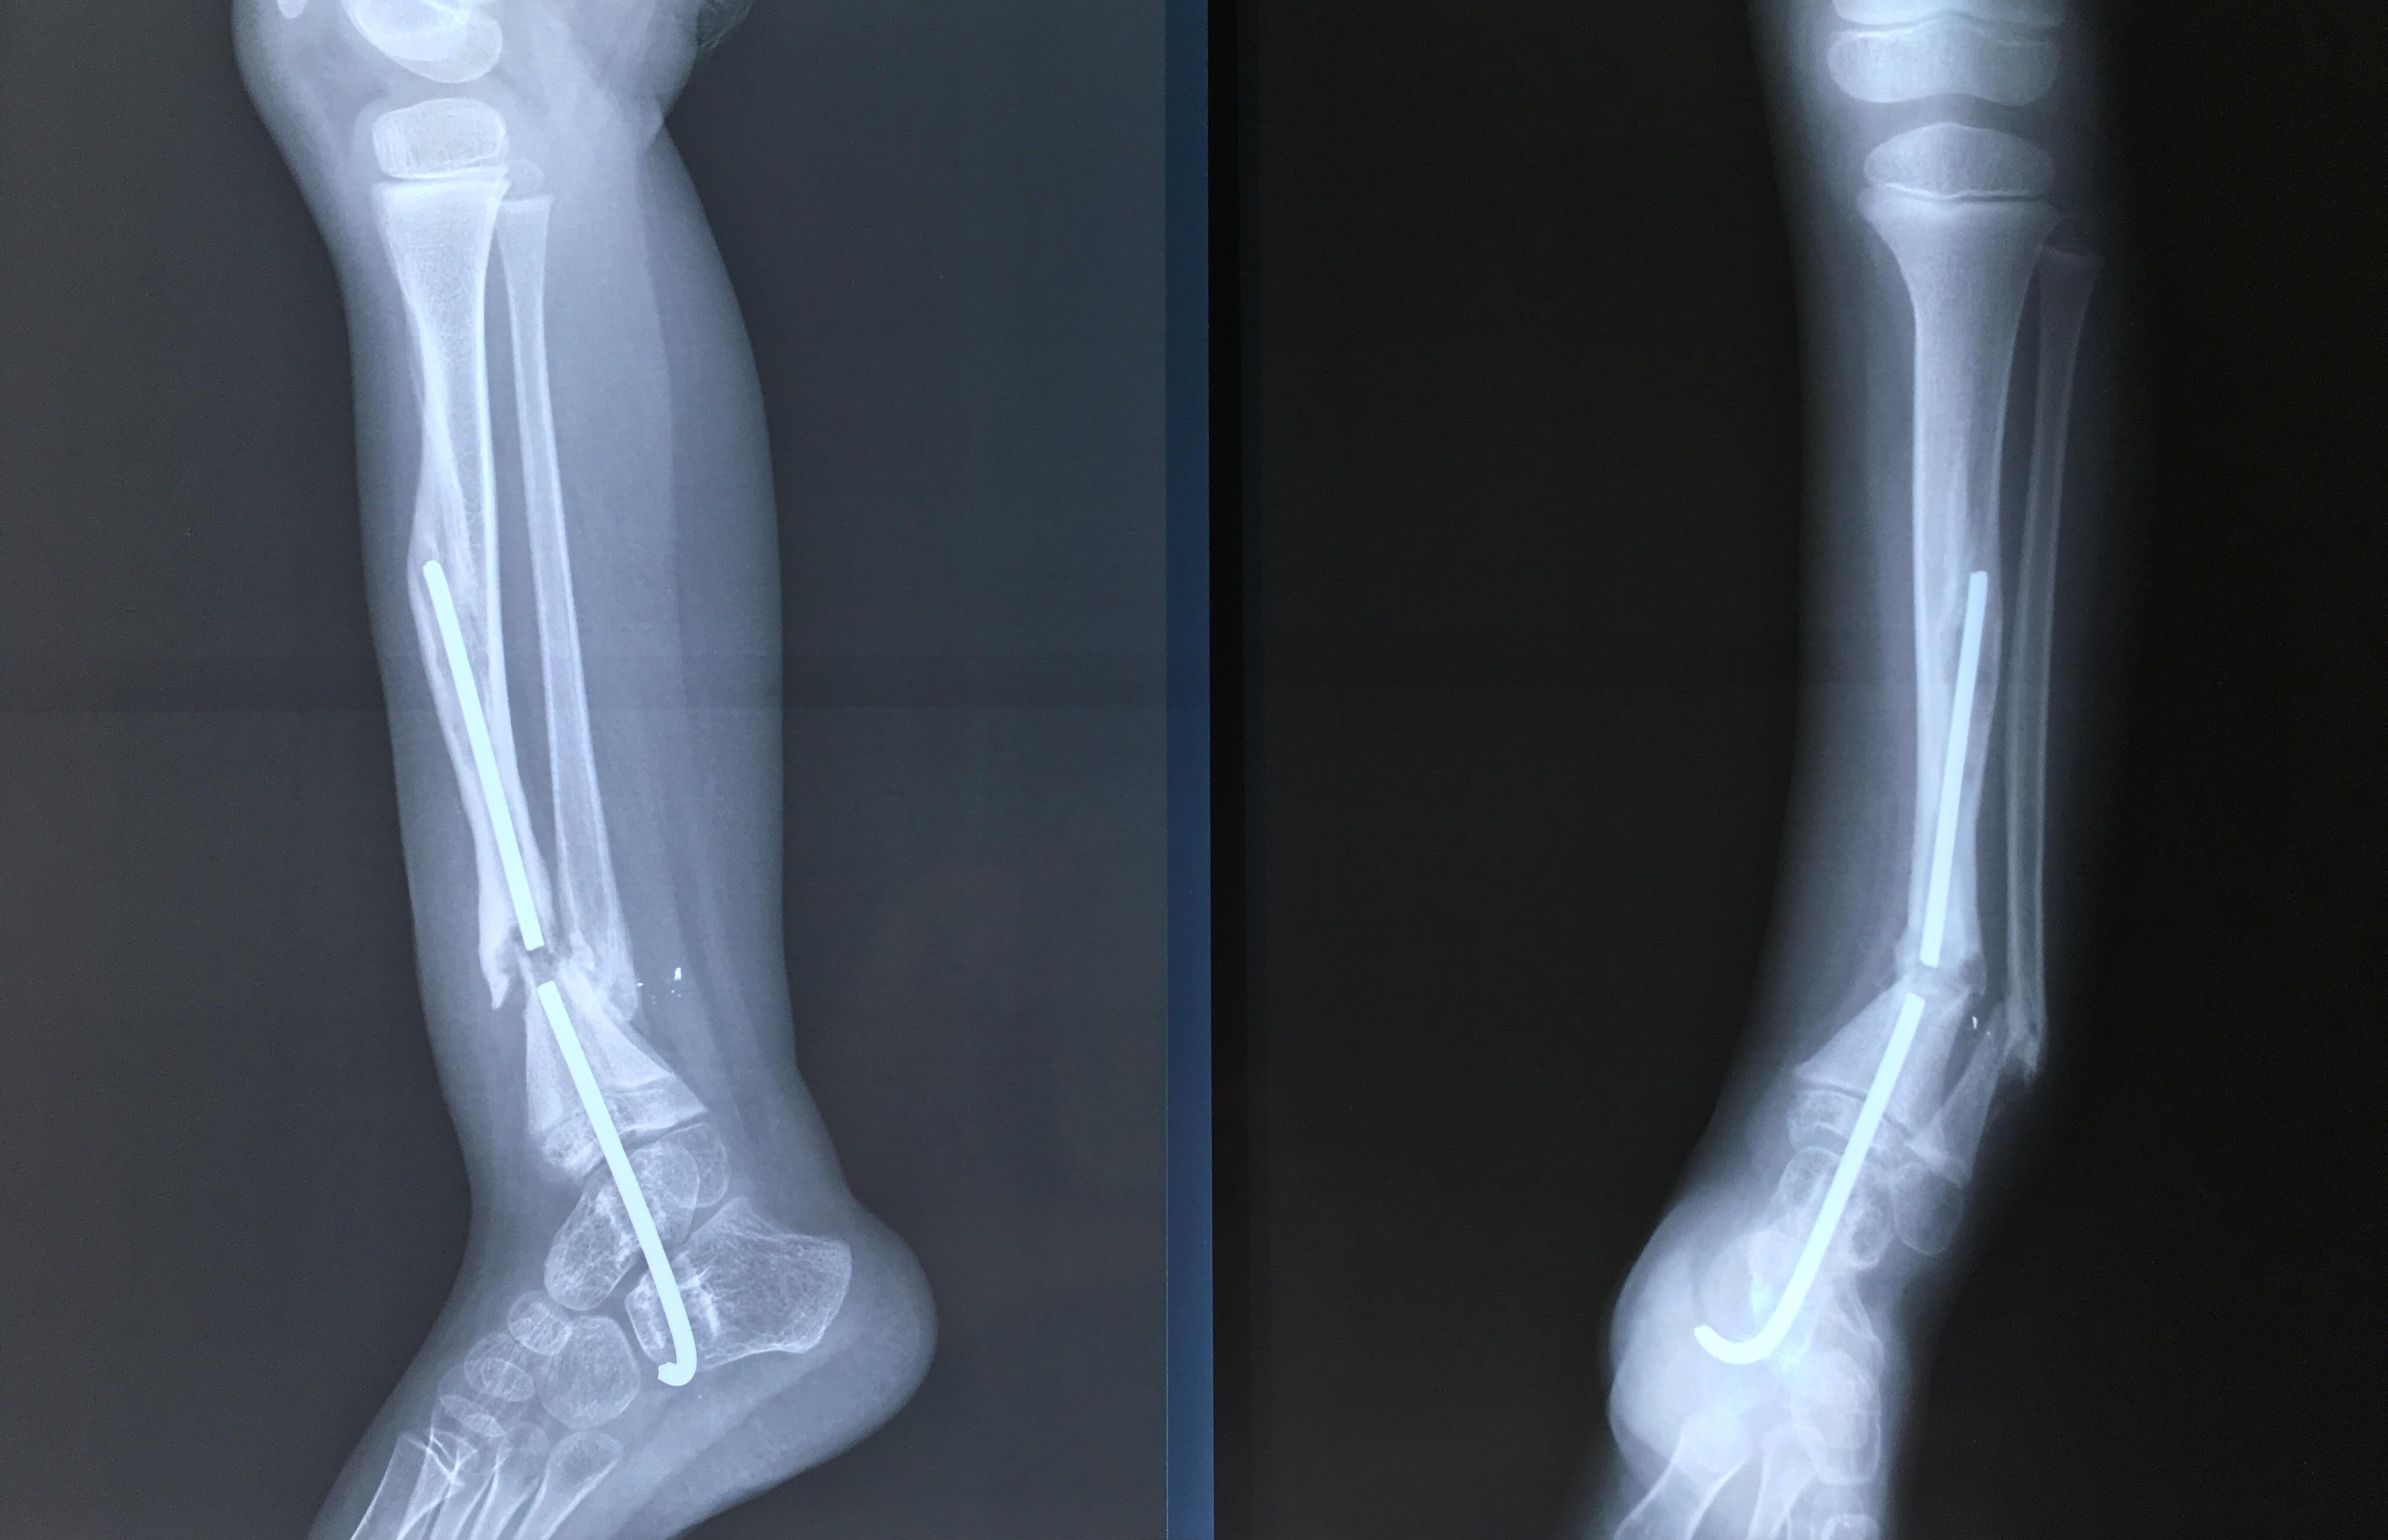

Phẫu thuật thành công ca bệnh hiếm gặp...khớp giả bẩm sinh xương chày

26/06/2019 17:00

Đã xem: 3381

Bệnh viện Chấn thương- Chỉnh hình Nghệ An, vừa phẫu thuật thành công cho bệnh nhi khớp giả bẩm sinh xương chày